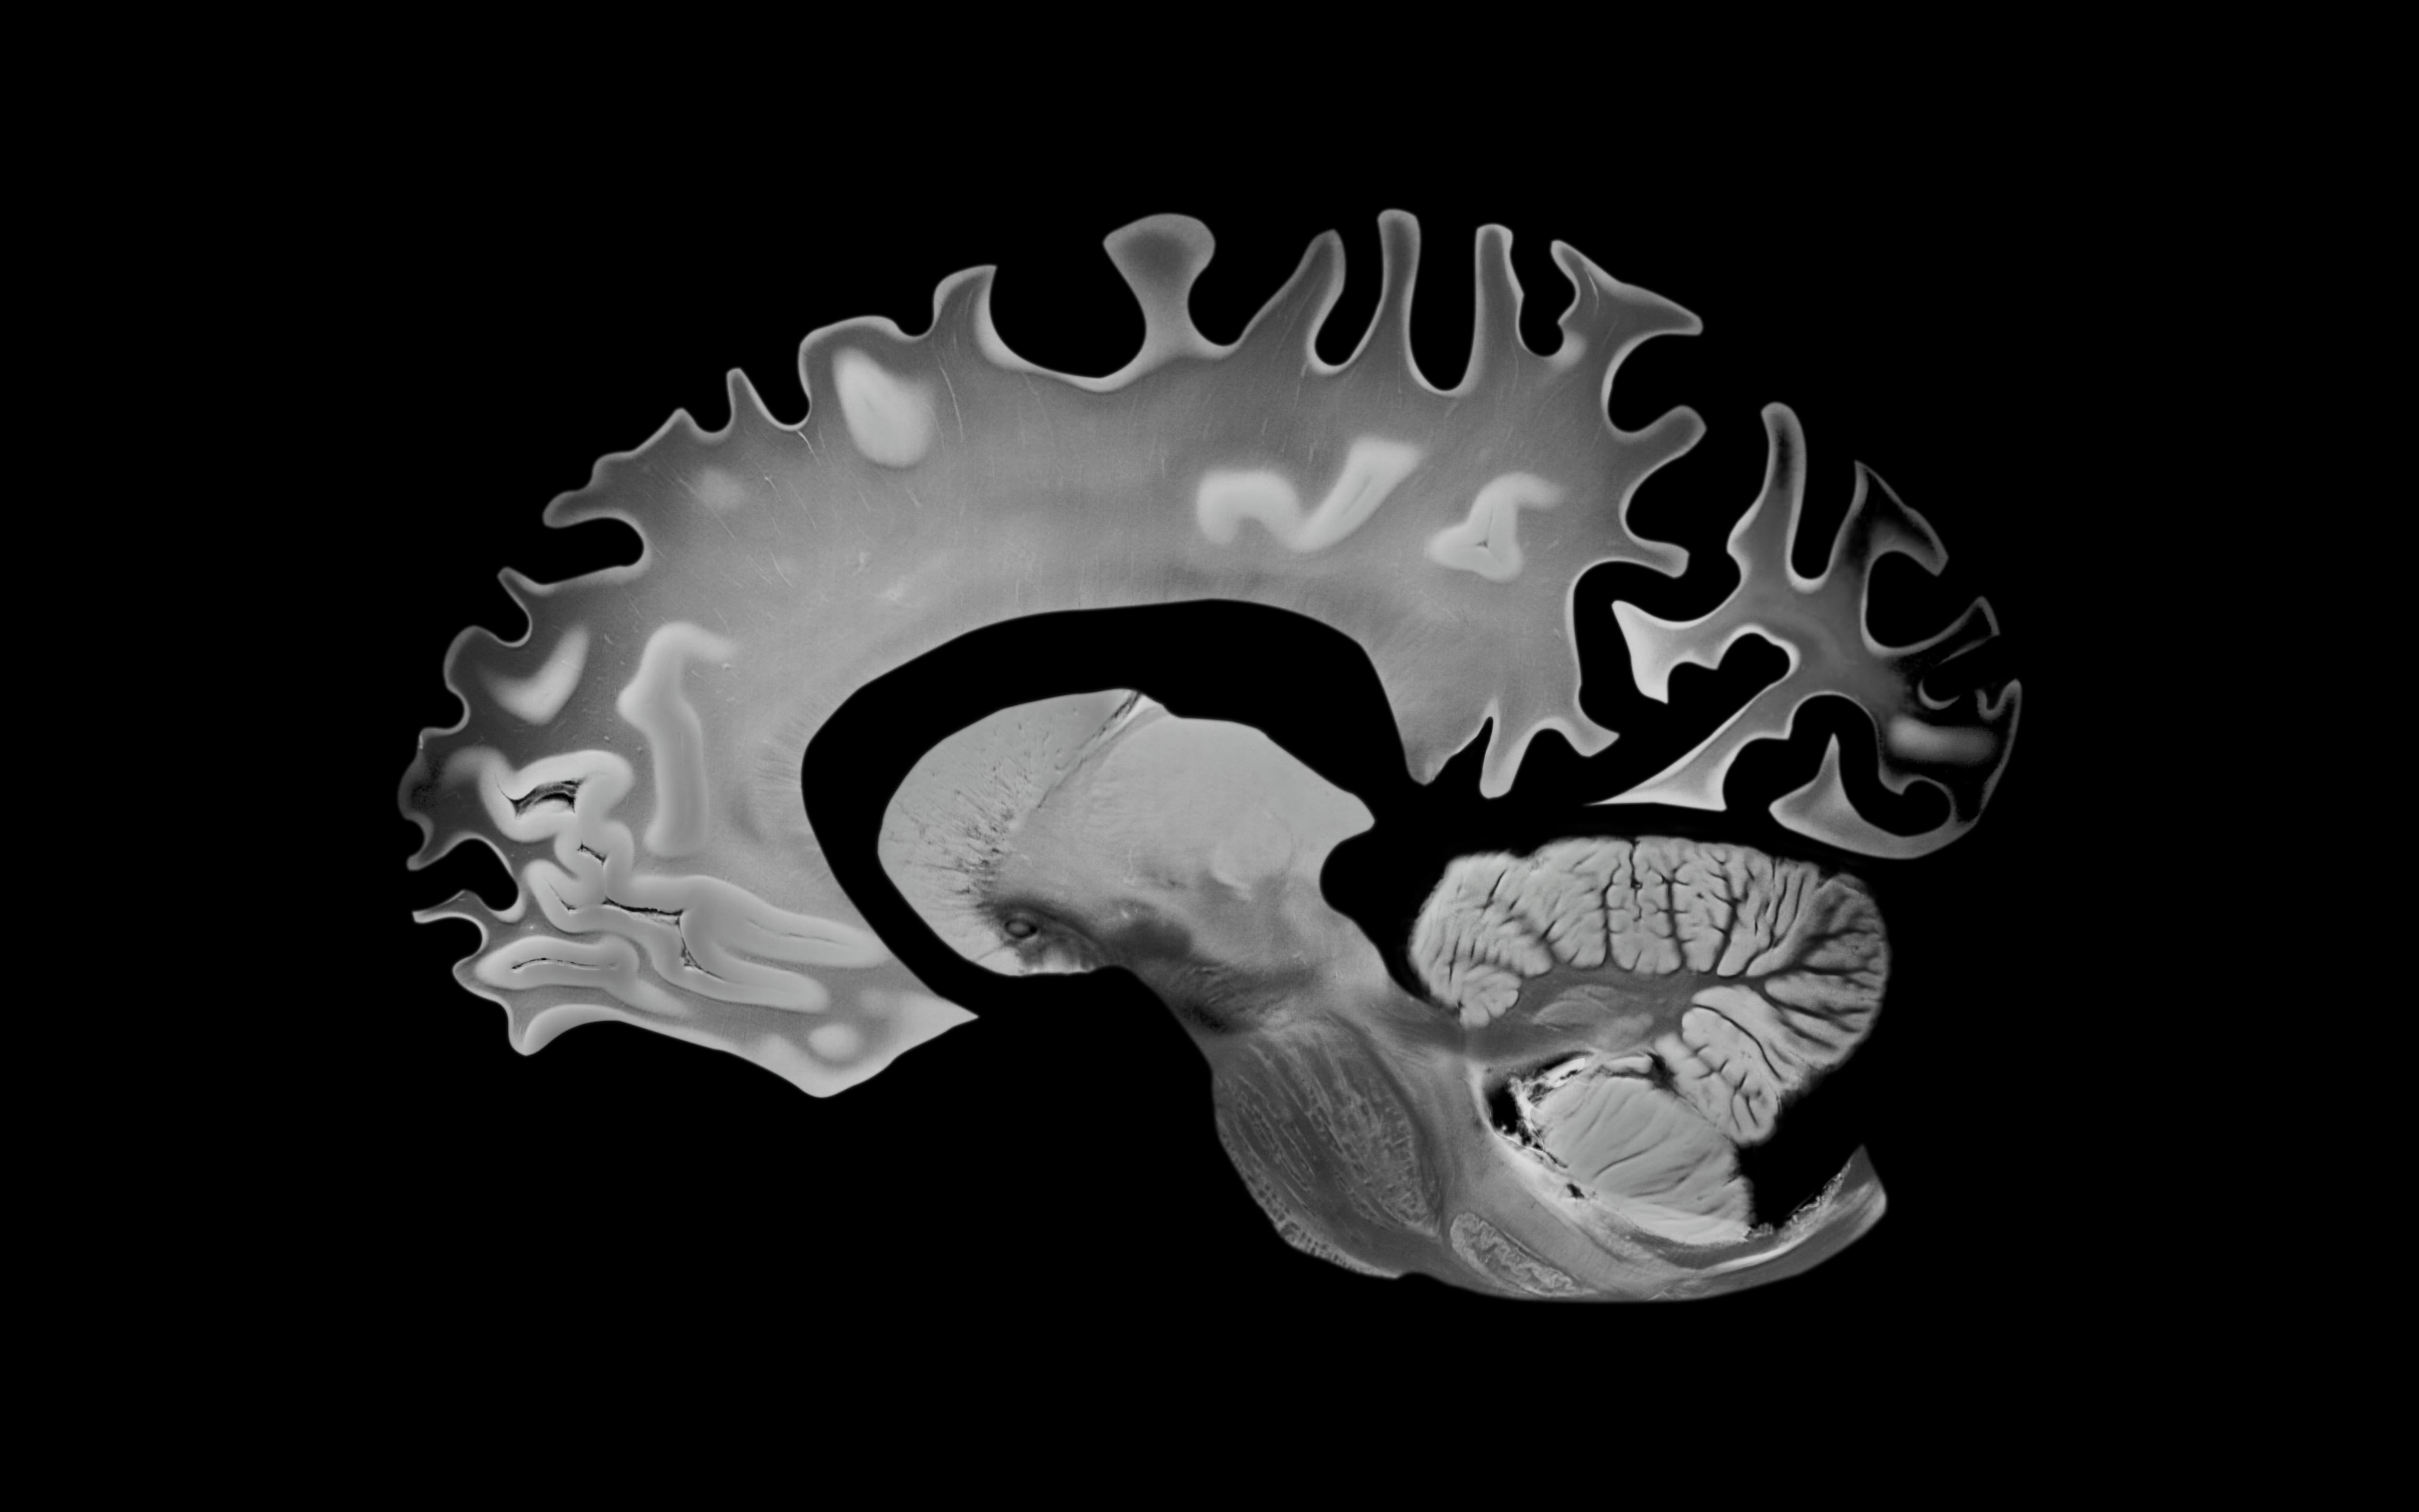

Neurologists Are Opening Up About Sleep Problems That Might Be Warning Signs Of Dementia

Experts reveal which sleep disturbances may signal something deeper, and when you should be concerned. This article originally appeared on HuffPost.